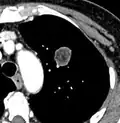

-

Part solid nodule.[9] -

Ground glass opacity nodule.[9]

- Pleural retraction is far more common in cancers.[9] It is the pulling of visceral pleura towards the nodule.[9]

Nodule with pleural retraction.[9] -

In this case, pleural retraction is seen as a triangular fat component.[9]

- A lung nodule abutting a pulmonary cyst is a rare finding, yet indicating cancer.[9]

- Bubble-like lucencies in the nodule indicate cancer:[9]